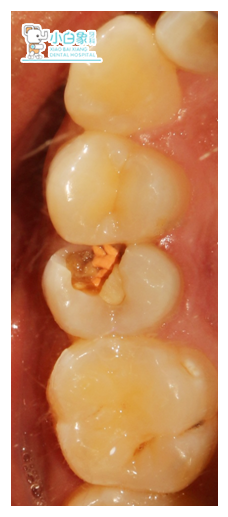

检查:合面及近中缺损达根管口,根管口见充填材料,叩(土),温度测试无反应,牙龈无红肿。

诊断:15无髓牙/慢性根尖炎